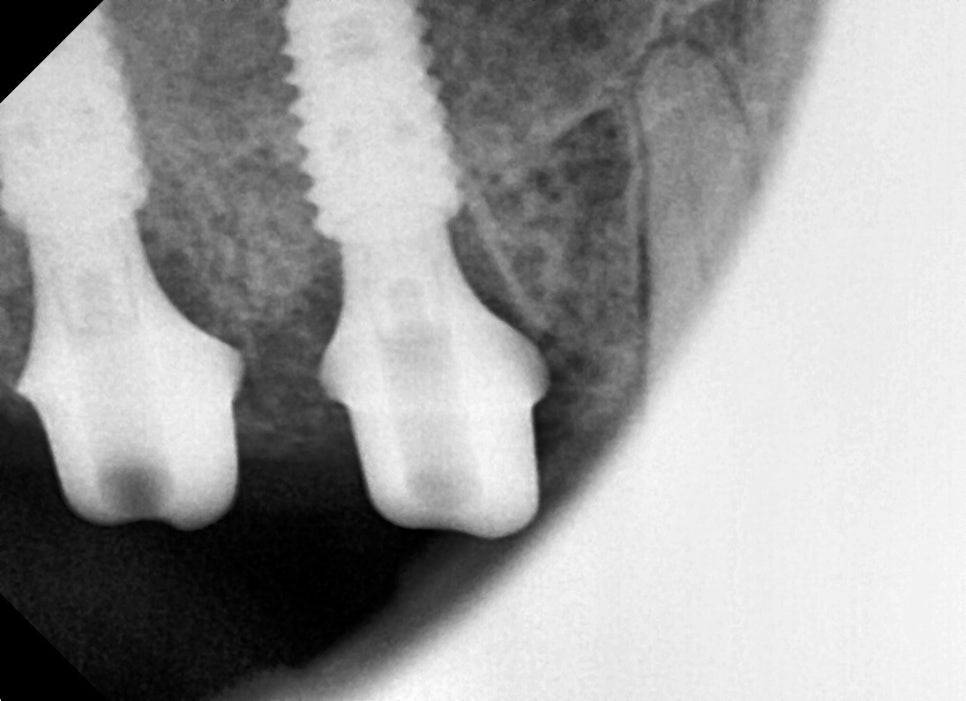

A detailed examination was carried out through panoramic imaging and CT scans.

The examination results showed not a simple cavity or crown fracture, but cracks extending to the root area.

If the crack extends to the root tip, it is difficult to save the tooth with conservative treatment,

and extraction followed by implant treatment should be considered.

At the follow-up visit, panoramic imaging confirmed that the implant was settling in well.